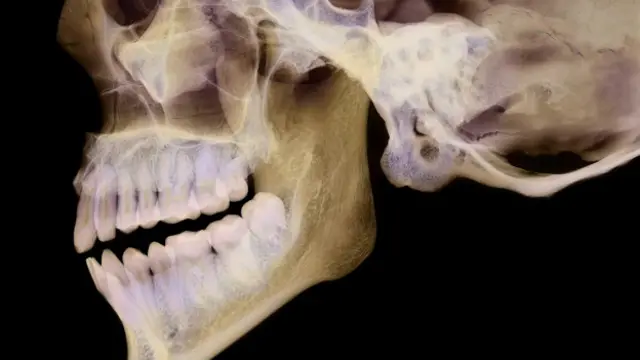

У нас есть некоторое представление о том, что такое подбородок. И всё же будет нелишним дать ему здесь краткое определение.

Попросту говоря, это выступ вдоль нижнего края челюстной кости человека. Ни у одного другого млекопитающего подбородочного выступа нет. У шимпанзе и других человекообразных обезьян, например, челюсти книзу скошены.

Как свидетельствуют данные археологических раскопок, ближайшие наши родственники, неандертальцы, тоже не имели подбородка.

Его присутствие или отсутствие в скелете лица используется поэтому как один из основных критериев отличия homo sapiens от homo neanderthalensis.